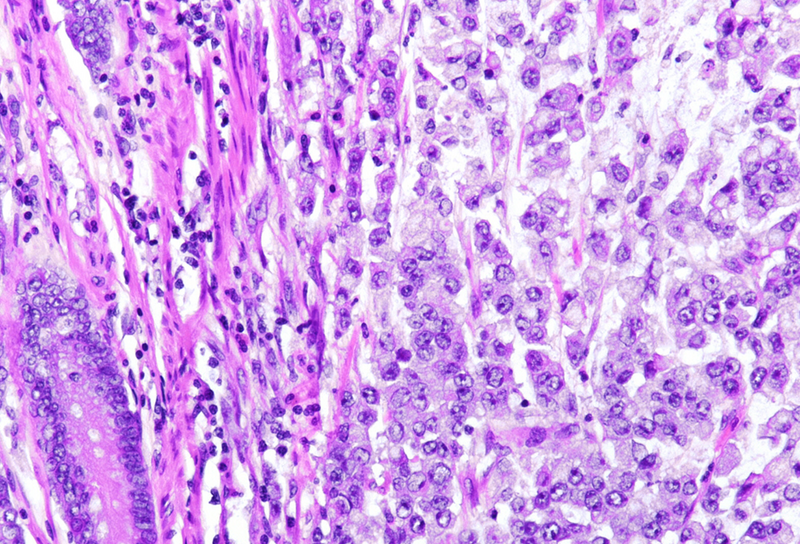

Histology showed a diffusely infiltrative solid neoplasm, extensively involving the colonic wall, with ulceration of the mucosa and extension into the subserosa. The tumor was composed predominantly of poorly differentiated neoplastic cells, isolated or in small clusters, displaying prominent intracytoplasmic mucin vacuoles displacing eccentric, hyperchromatic nuclei to the periphery (Panels A-C), features diagnostic of signet-ring cell morphology. Focal areas showed extracellular mucin lakes, but no conventional gland-forming adenocarcinoma component was identified. Prominent lymphovascular invasion was evident. No lymph nodes with metastases were found.